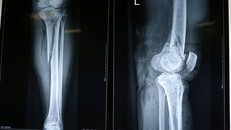

Bất cẩn trong lúc tham gia giao thông, bệnh nhân L.T.P đã bị tai nạn giao thông khiến gãy chân và tổn thương mạch máu phải nhập viện cấp cứu.